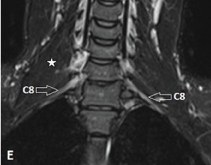

| Figure 1: Normal MR imaging planes and appearance of BP. A-F, Acquisition of the coronal plane with fat-suppressed T2-weighted anterior (D), mid (E), andposterior (F) coronal sections. First a coronal cervical spine scout is obtained (A), based on this a sagittal T2-weighted spin-echo sequence of the cervical spine isacquired (B). Now based on this sagittal image, coronal fat-suppressed T2-weighted and T1-weighted sequences are obtained in a plane parallel to the long axis ofthe lower cervical vertebrae (C) because the BP is oriented in an oblique coronal plane. On coronal fat-suppressed T2-weighted sequence, long axis of the nerveplexus is seen as elongated, uniform calibre, mildly hyperintense fascicular structure. On the anterior coronal image, normal C5, C6, C7 nerve roots (open arrows)are seen on the right side; on the left, the upper (UT), middle (MT) and lower trunks (LT) (solid arrows) are seen (D). At the level of middle scalene muscle (star), onthe mid-section, C8 ventral ramus (open arrows) is seen bilaterally (E), while the T1 nerve root (open arrows) is visualized completely on the posterior section (F). | |